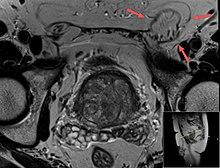

Ultrasound of an indirect hernia containing fat, with testicle seen at right.

T2 weighted MRI of the same case (done for another purpose), also demonstrating fat content.

An indirect inguinal hernia results from the failure of embryonic closure of the deep inguinal ring after the testicle has passed through it. It is the most common cause of groin hernia.

When assessed by ultrasound or cross sectional imaging with CT or MRI, the major differential in diagnosing indirect inguinal hernias is differentiation from spermatic cord lipomas, as both can contain only fat and extend along the inguinal canal into the scrotum.[22]

On axial CT, lipomas originate posterolateral to the cord, and are located inside the cremaster muscle, while inguinal hernias lie anteromedial to the cord and are not intramuscular. Large lipomas may appear nearly indistinguishable as the fat engulfs anatomic boundaries, but they do not change position with coughing or straining.[22]